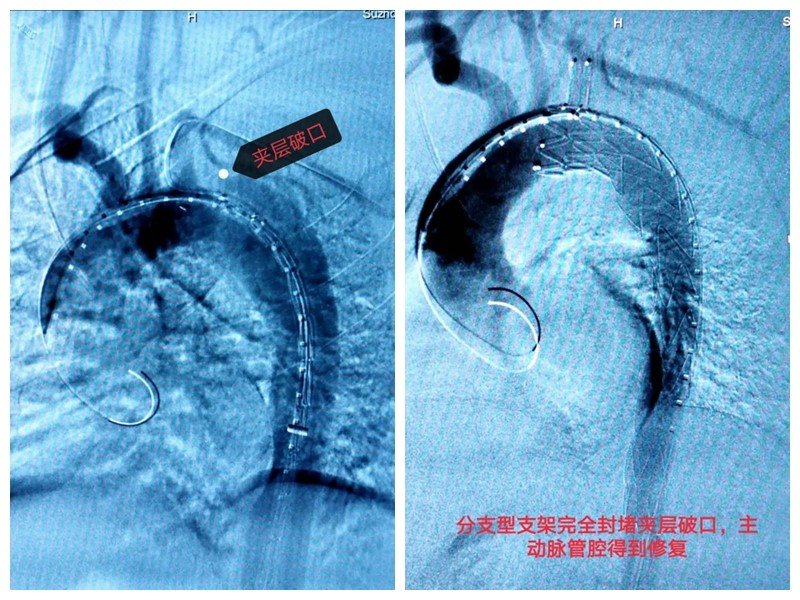

▲手术前(左),手术后(右)

手术方案得到了九龙医院院长钱海鑫的同意。随后,李强和他的团队为手术做起了准备:降压、控心率、镇静镇痛……医护人员的严谨到位,为保障患者安全提供了有力支持。手术前,李强根据CT图像,对小邹撕裂的大动脉进行了反复且精准的测量,并为其选择了一款规格大小合适的分支型覆膜支架。由于前期准备充分,手术进行得十分顺利,支架在小邹的体内被成功释放,完全封堵住了主动脉夹层破口,巨大的“假腔”消失了,左锁骨下动脉血流保持通畅,肝、脾、肠等重要脏器血流恢复为“真腔”供血。手术持续了1个小时,小邹体内的这颗“不定时*弹炸**”被成功拆除。术后,他被转入介入血管外科普通病房,生命体征平稳,很快就可以下床活动了。经过几天的观察,小邹办理了手续,顺利出院了。